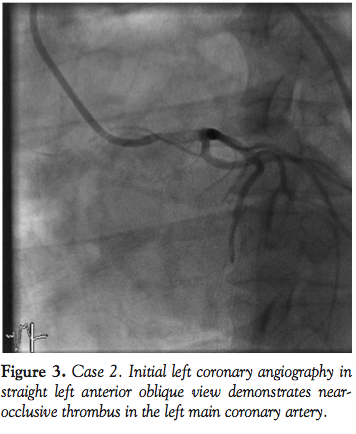

Case 2. A 40-year-old female with a history of hypothyroidism was in a local office when she experienced the sudden onset of crushing chest pain. Emergency medical services (EMS) performed a pre-hospital ECG demonstrating significant ST elevations in leads I, aVL, aVR, and V4-V6. On arrival to the emergency department, she was somnolent with a blood pressure of 114/70 mm Hg and heart rate of 90 bpm. Her ECG evolved into a wide right bundle branch block with anterior STEMI. She was brought to the CCL emergently and

her initial systolic central blood pressure was 50 mm Hg. Left coronary angiography demonstrated occlusive thrombus extending across the length of the left main coronary artery with only TIMI 2 distal flow and minimal movement of the cardiac silhouette (Figure 3). As her hemodynamics continued to deteriorate, manual guide catheter aspiration and guidewire manipulation dislodged the thrombus with minimal thromboembolism to the apical LAD (Figure 4). Her cardiac motion on fluoroscopy